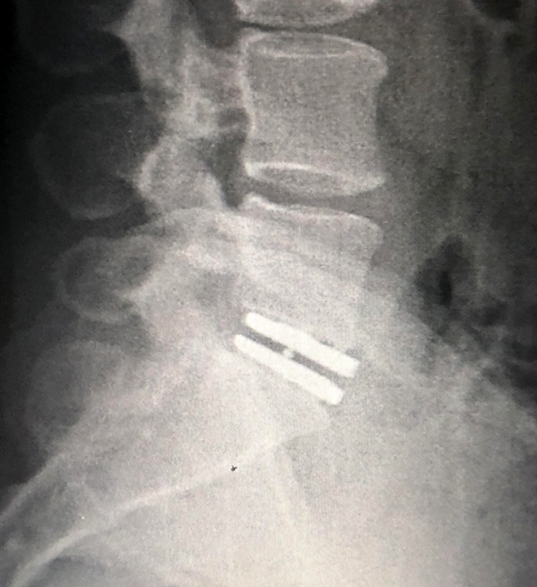

Un disco artificial es un dispositivo qué está formado por dos planchas de titanio, una superior y otra inferior qué van adheridas a las vértebras. Entre estas planchas hay un núcleo de plástico que se desplaza y permite el movimiento de las vértebras bien sea en el plano coronal (lateral) o el plano sagital (antero-posterior). De esta manera se preserva el movimiento al segmento o disco operado, manteniendo la fisiología de la columna lo más normal posible. La otra opción al disco artificial es una caja intersomática anterior que se conocen como ALIF por sus siglas en inglés (Anterior Lumbar Interbody Fusión). Estas cajas se usan mucho y tienen sus indicaciones precisas, pero son rígidas, es decir, eliminan el movimiento entre las vértebras.

El disco artificial no puede utilizarse en todos los pacientes, debe haber ciertas condiciones que permitan utilizarlo. Las variables que determinan si se puede usar o no el disco artificial, se determinan con la evaluación de los estudios de rayos X de la columna, la resonancia magnética nuclear y la densitometría ósea. Hay paciente que no son candidatos para discos artificiales y en ellos se usan las cajas intersomáticas.